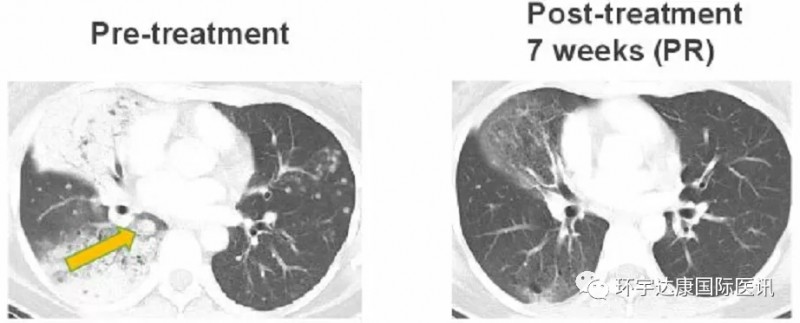

NO.2、有效克服克唑替尼耐药

一位38岁的女士确诊为CD74-ROS1融合阳性非小细胞肺癌,之前接受过化疗和克唑替尼的治疗,但是出现了一种新的耐药突变ROS1G2032,患者接受Taletrectinib(600mg,QD)治疗,在第7周时,肺部肿瘤迅速缩小,评效为部分缓解(PR),目前该患者仍在接受治疗中。